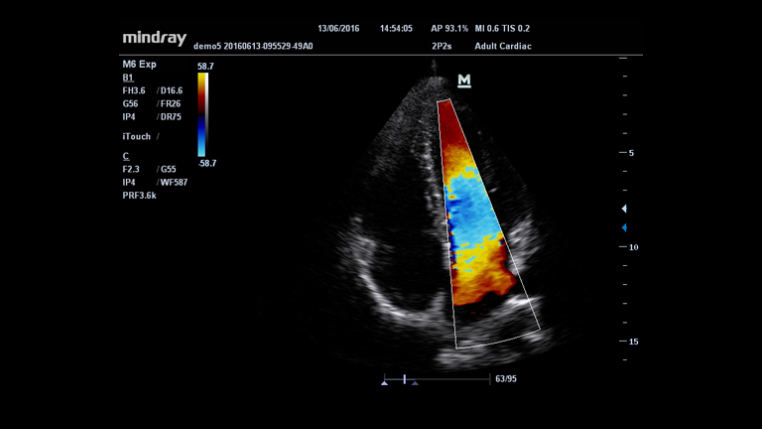

HR Flow?

?????? ???? ???? ????? ???? ??? ? ??? ?? ??? ?? ??? ???? ? ?? ???? ?????.